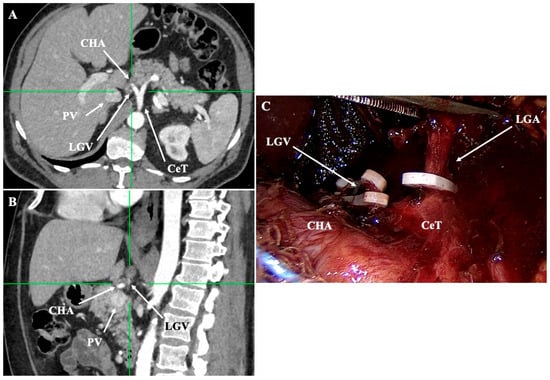

- Lesser curvature and suprapancreatic corridor (stations 7, 8a, 9, 11p): the LGV most often courses posterior to the CHA or anterior to the LGA; recognizing this pattern helps avoid avulsion during high ligation of the LGA and station-7 dissection [30]. Classify the LGV preoperatively relative to the CHA/SA/pancreas. Intraoperative video-based classification in 217 laparoscopic radical gastrectomy cases found type I (LGV running between the CHA posteriorly and the CA-Figure 4) to be most common (56%), whereas type IV (between SA posteriorly and CA-Figure 5) carried the highest bleeding risk (42%) and was an independent predictor of LGV injury on multivariable analysis [32,45] (Figure 4 and Figure 5). 3D MDCT classifications also emphasize that the LGV may terminate variably into the PV, SV, or their confluence—information that guides safe exposure at the pancreatic head and coeliac axis [40]. When a replaced/accessory left hepatic artery arises from the LGA, D2 dissection must preserve arterial inflow while clearing nodal tissue—an approach illustrated in operative atlases focused on variation-aware D2 technique [6].